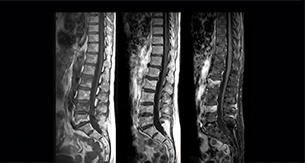

Spine scans must be fast and complete

“In our spine cases, we use mDIXON TSE for patients with degenerative and inflammatory spine issues, vertebral fractures and vertebral and paravertebral tumor characterization,” says Dr. Lefebvre. “It provides, in a single acquisition, different contrasts so we can both visualize and characterize spinal, focal or diffuse spine lesions.”

“mDIXON TSE makes real a difference in cases of acute and traumatic spinal injuries, where it allows us to reduce the scan time by only using a limited number of sequences. For patients in pain, who come from the emergency unit and need surgery, for example, MRI must be very fast. With a single T2-weighted acquisition we can assess spinal cord, vertebral disc and ligament wholeness with in-phase images, as well as trabecular fracture and edematous changes with water images.”

Dr. Lefebvre cites other frequent examples of spinal diseases that benefit from the mDIXON technique. “In cases of vertebral disc herniation or degenerative discs, for example, we don’t have to choose between fat or no fat images. We can assess morphological changes in the endplate with in-phase images from T2-weighted sequences and in the water image from the same acquisition we will see inflammatory changes into endplates.”

“We can both visualize and characterize spinal, focal or diffuse spine lesions.”